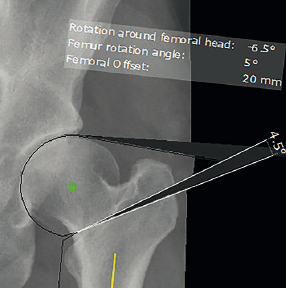

Chức năng “Intertrochanteric osteotomy” cho phép bác sĩ phẫu thuật lập kế hoạch cắt xương chính xác đối với vùng mấu chuyển xương đùi. Dựa trên các sai lệch của trục chi, chức năng “Intertrochanteric osteotomy” có thể đưa ra gợi ý tới khả năng bảo tồn trì hoãn hay bắt buộc phải thay khớp háng.

Chức năng này cho phép lập kế hoạch đường cắt xương dọc theo khối mấu chuyển, cùng với việc xác định góc xoay của mặt cắt xương.

Việc phẫu thuật xương được lên kế hoạch sử dụng góc xoay này được tạo ra trong hình ảnh đã lên kế hoạch. Các bác sĩ phẫu thuật lập kế hoạch cắt xương chính xác đối với vùng mấu chuyển xương đùi. Dựa trên các sai lệch của trục chi, chức năng “Intertrochanteric osteotomy” có thể đưa ra gợi ý tới khả năng bảo tồn trì hoãn hay bắt buộc phải thay khớp háng.

Chức năng này cho phép lập kế hoạch đường cắt xương dọc theo khối mấu chuyển, cùng với việc xác định góc xoay của mặt cắt xương. Việc Phẫu thuật chỉnh hình xương 3D được lên kế hoạch sử dụng góc xoay này được tạo ra trong hình ảnh đã lên kế hoạch.

Các bác sĩ phẫu thuật có thể sử dụng hình ảnh này để điều chỉnh linh hoạt góc cắt của xương. Nó cũng có thể mô phỏng xoay chỏm xương đùi. Các thiết bị kết hợp xương, chẳng hạn như đinh, nẹp hoặc vít, có thể được chọn một cách thuận tiện từ cơ sở dữ liệu